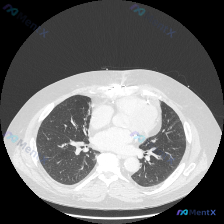

胸部CT影像矛盾分析:肺窗无异常 vs 提及结节

首先是影像检查信息:这是胸部CT肺窗的横断面,报告提到双肺透亮度均匀,未见弥漫性磨玻璃影、实变或肺气肿;肺纹理清晰,支气管血管束走行正常;双侧胸膜光滑,纵隔居中,肺野清洁,未观察到结节、肿块等局灶性病变。

但输入里明确说了“Nodule(结节)”,这里就有直接矛盾了。这个矛盾是分析的起点,可能的原因有几个方向:

- 结节信息来源其他检查,比如体检、胸片或其他影像层面

- 结节在当前CT图像的其他层面,单张肺窗不能代表全肺

- 对当前图像的解读有差异

假设结节存在,鉴别诊断需要更多信息,比如结节的大小、形态、密度、位置,还有患者的年龄、吸烟史、症状、免疫状态等。但现在信息冲突,这些都没法展开。

这里容易踩的陷阱是确认偏见,只接受符合初步印象的信息,忽略相反的证据,或者锚定在“有结节”的描述上影响客观评估。最佳策略是先核实信息,建立可靠事实基础,再进行病因分析。